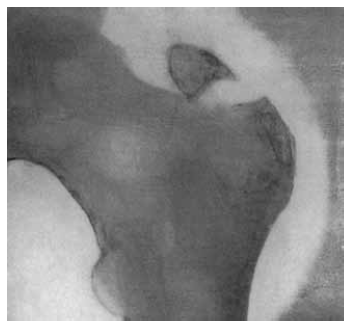

Canadian orthopedic surgeon G.E. Armstrong reported the first clinical case of GT fracture with a radiological pattern and detailed description of the circumstances of the injury [5]. In his study, the patient J.M., 33 years old, was admitted to the Monreal General Hospital on November 3, 1906; the patient presented with complaints of pain and limited range of motion in the right hip joint. The result of the radiological examination of the patient at the time of admission is presented in Fig. 1.

Fig. 1. Radiograph of the right hip joint in the posteroanterior view